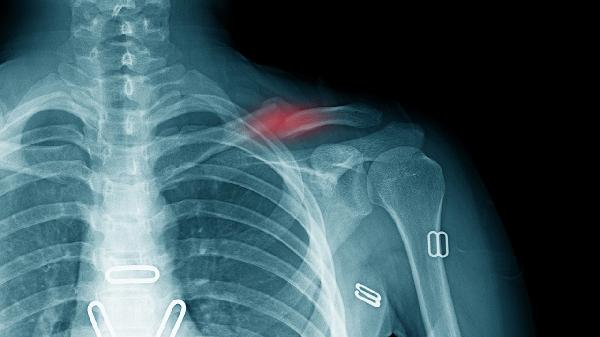

密切观察患肢末梢循环、感觉及运动功能,如出现持续疼痛加剧、皮肤温度降低或足背动脉搏动减弱,需警惕骨筋膜室综合征。定期复查X线确认骨折对位情况,发现夹板移位或固定失效应及时调整。